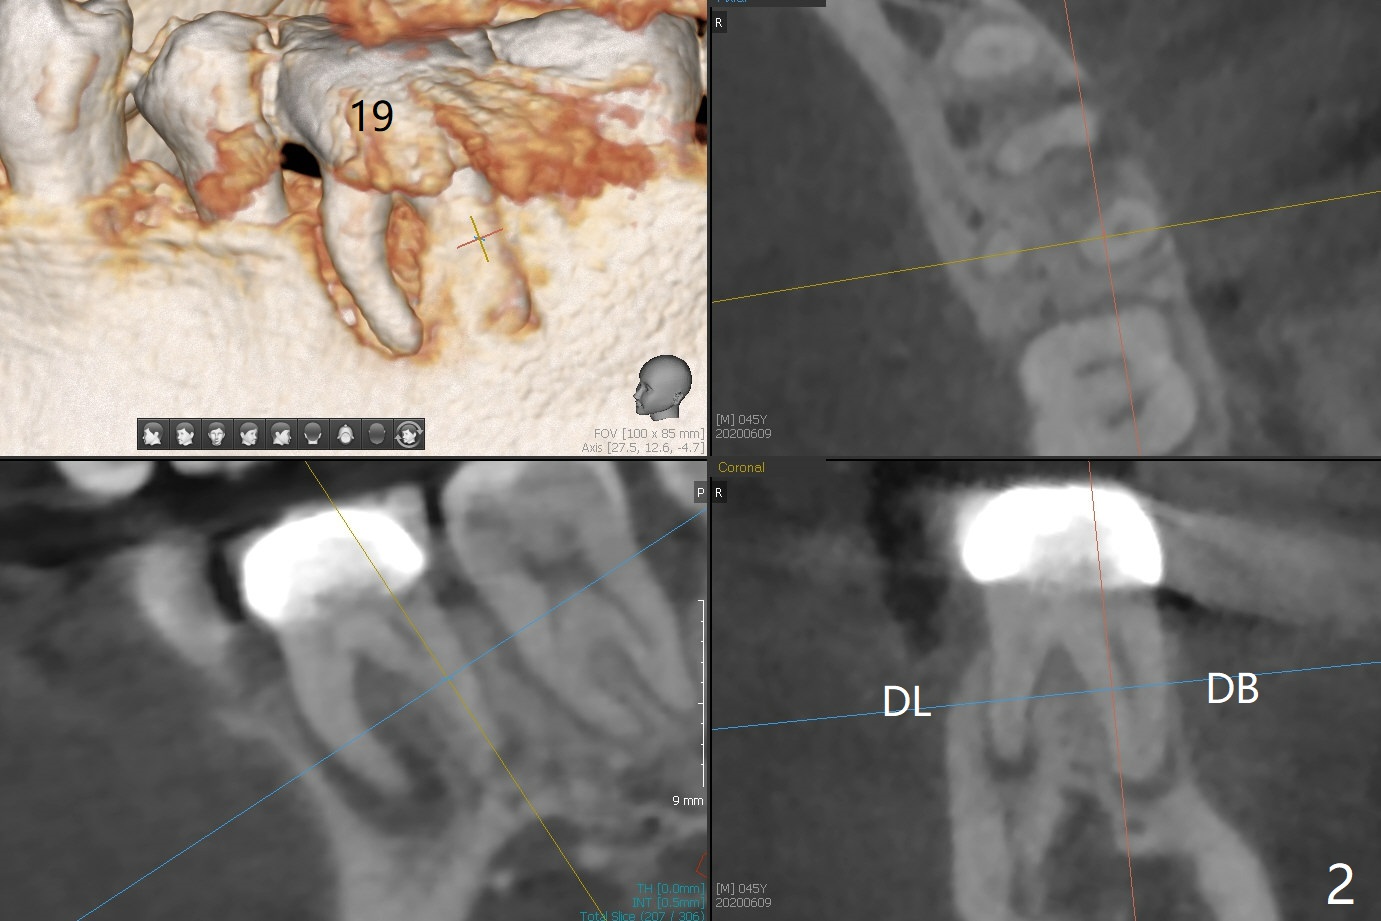

A 45-year-old man requests extraction of #19 because of endodontist's diagnosis of root fracture (Fig.1). CT shows typical apical periodontitis (Fig.2) without sign of root fracture (profilogram, data not shown), although the buccal plate of the mesial root is lost (Fig.3). Ideally 2 implants should be placed in UR and LR quadrants to prevent #19 root fracture after RCT (Fig.4). Alternative way is to place an implant at #3 (5x7.3 mm) and #30 immediately after #31 extraction. In fact a surgical guide for #30 will be fabricated resting the distal aspect of the tilted tooth #31 after sectioning the mesial portion in the lab (Fig.1 red line).